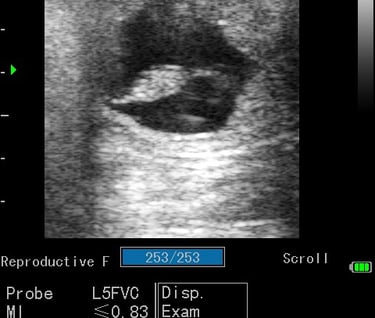

Gynécologie